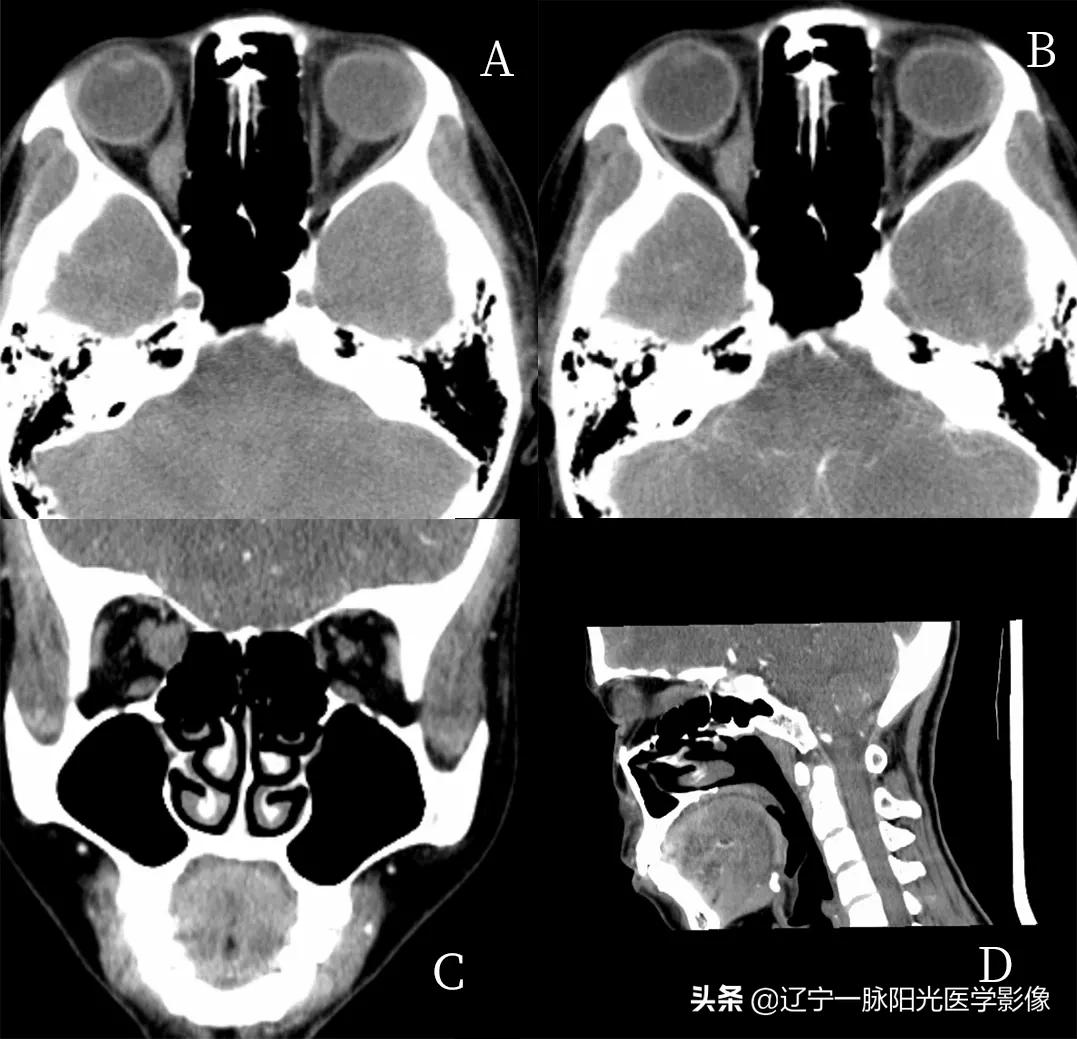

图 A 平扫轴位示右侧内直肌增粗,形成类圆形软组织影,大小约为 1.3×0.7 cm,平扫呈低密度,CT 值约 45 HU

图 B、C、D 增强轴位、冠状位、矢状位示病灶中度强化,CT 值约 53 HU,眼球未见明显受压移位,泪腺结构未见明显异常,骨质结构未见明显破坏

最终病理诊断为肌炎型炎性假瘤

影像所见;:

图 A、B 轴位示右侧眼球稍向前突,球后充盈团块状软组织信号影,范围约 4.3 cm×3.5 cm, T1WI、T2WI 呈低信号

图 C 示 DWI 亦呈低信号

图 E、F 增强后呈不均匀明显强化,其内见环行强化,病灶包绕右侧视神经及眼肌

病理诊断:炎性假瘤